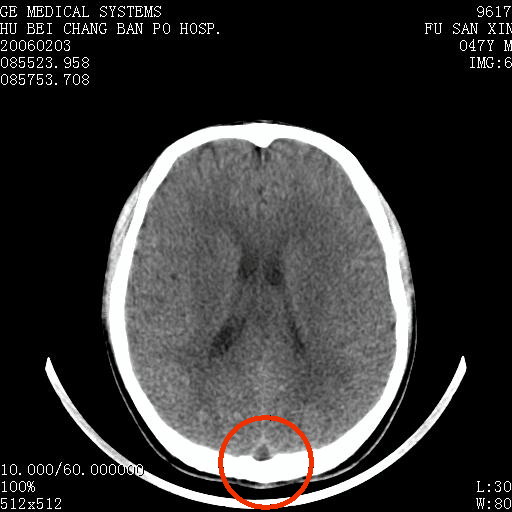

男 47岁 头痛多年,眩晕、呕吐一天,无明显神经系统症状。头颅ct部分层面显示双侧筛窦,右侧额窦炎。

下图中红圈里上矢状窦的三角形低密度影如何解释?